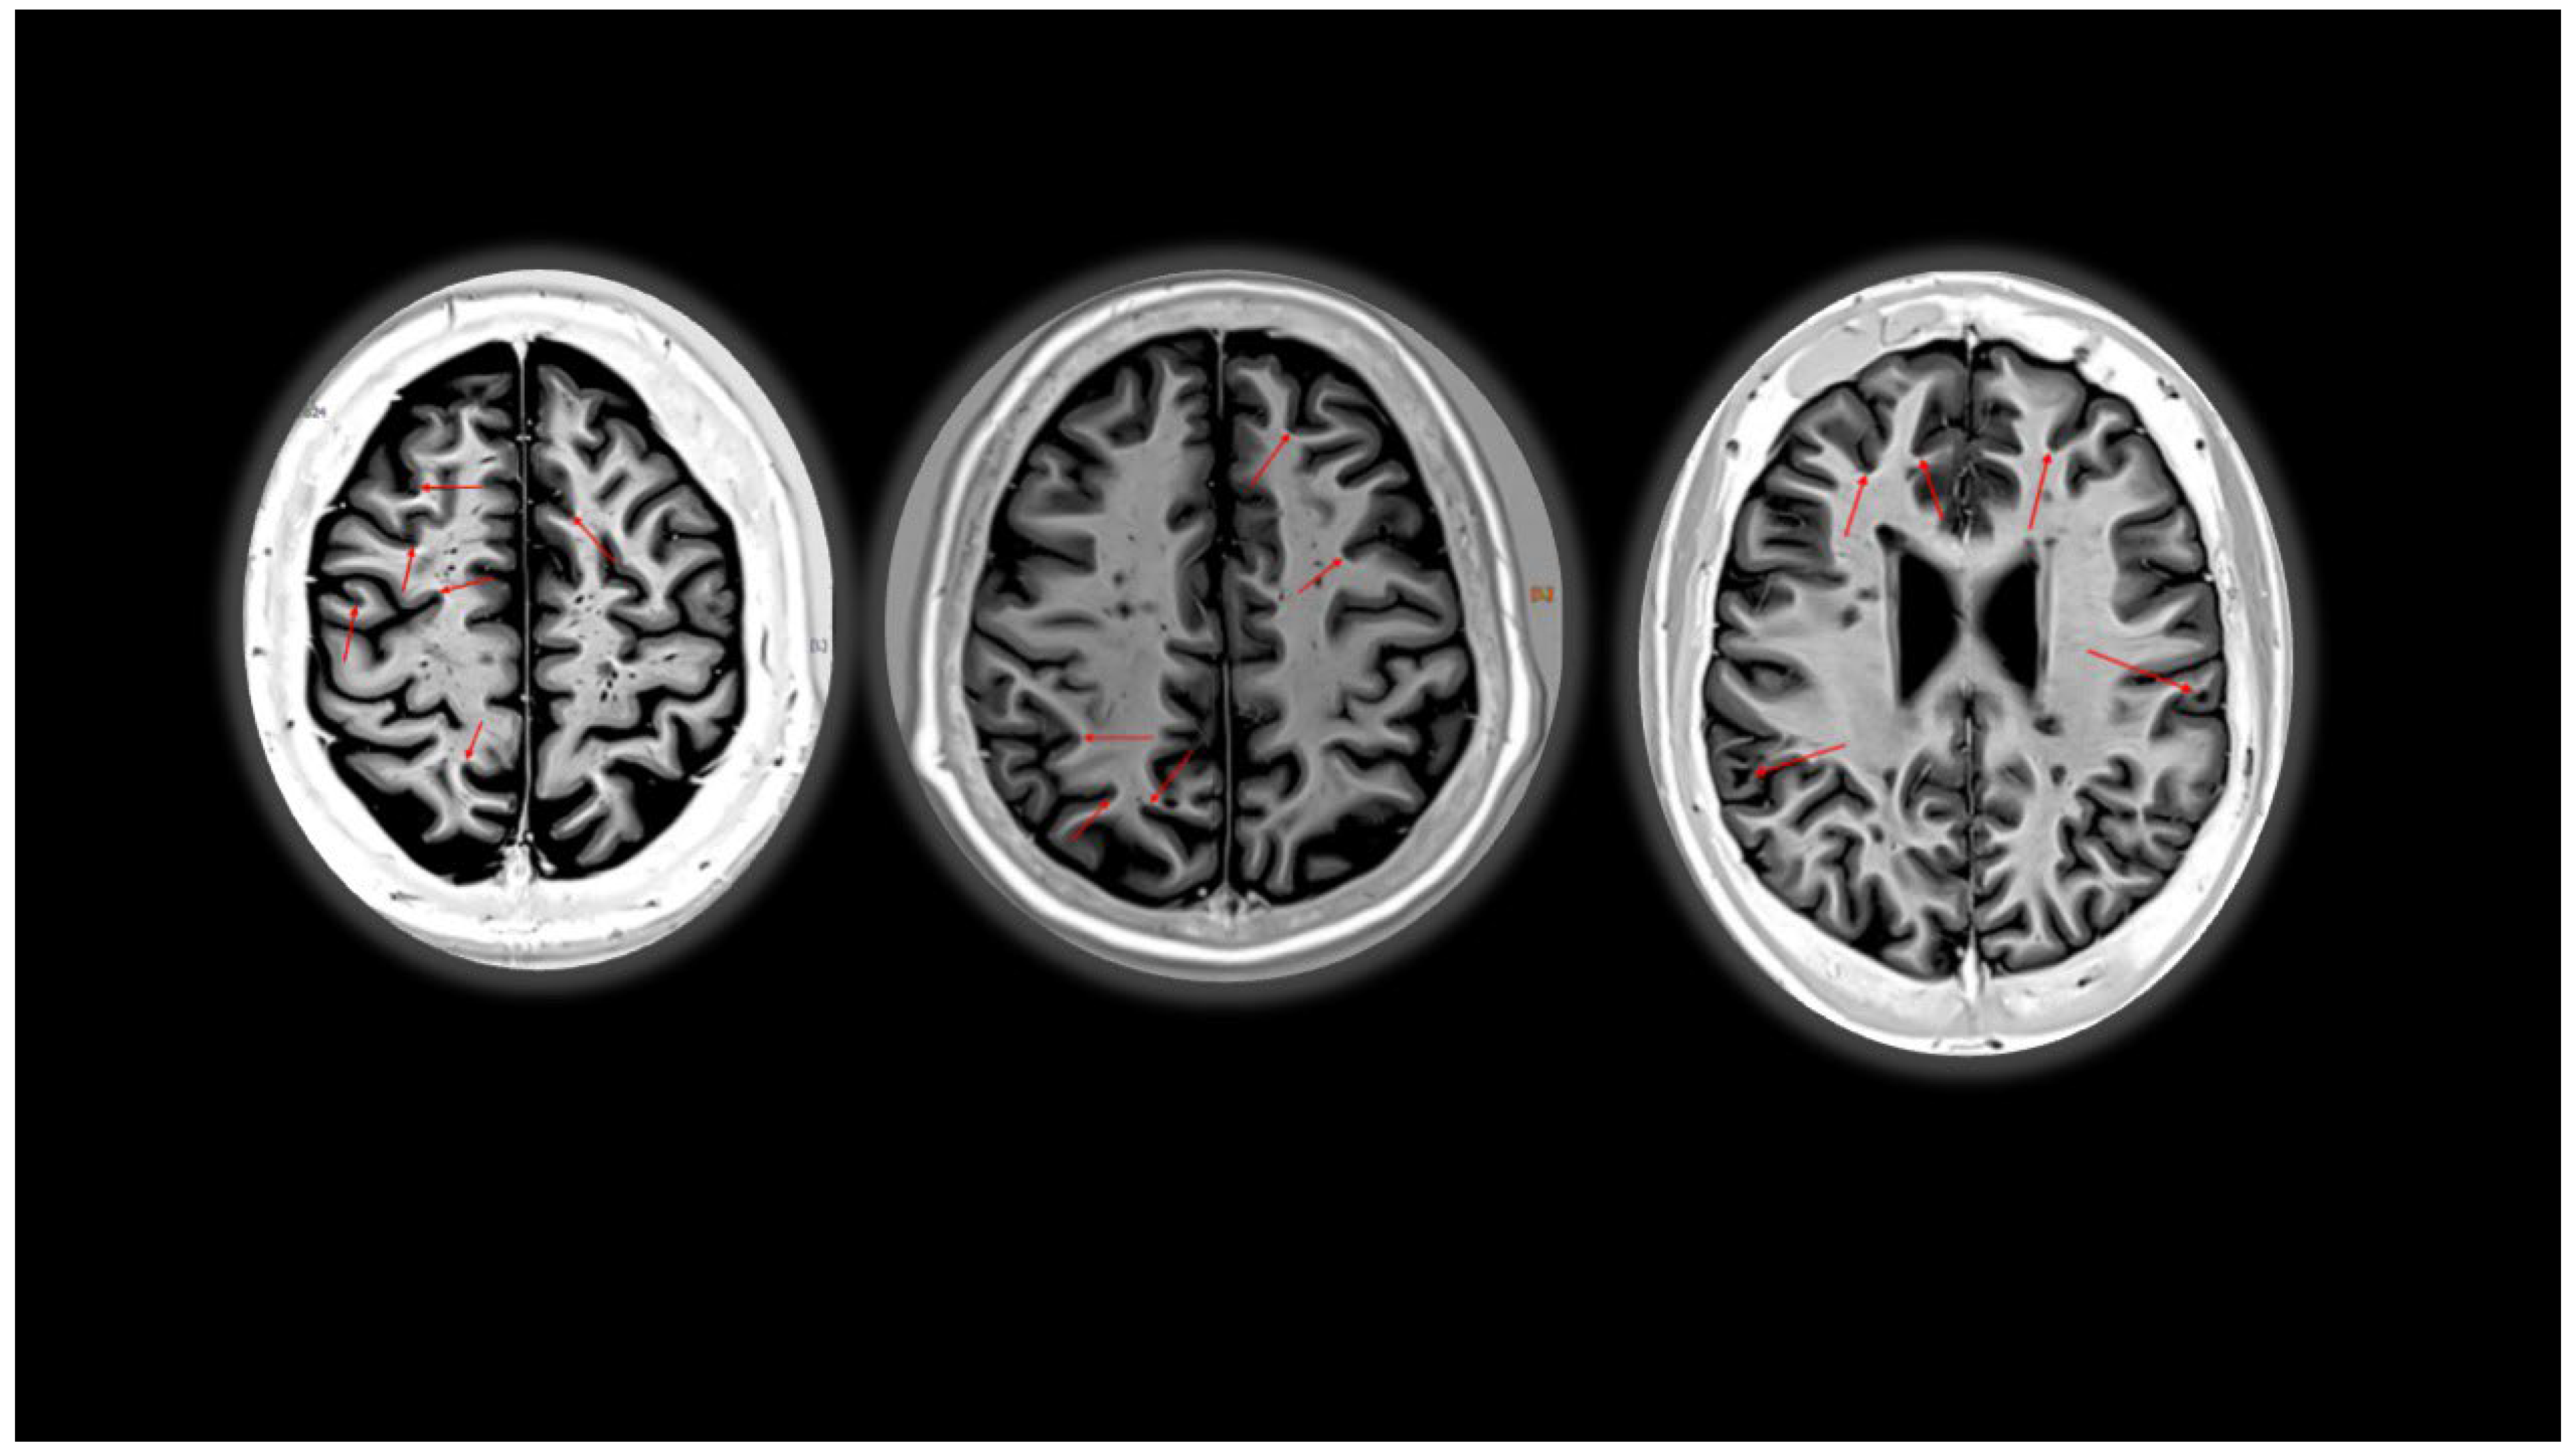

2. Cortical Lesions

- La Rosa, F.; Abdulkadir, A.; Fartaria, M.J.; Rahmanzadeh, R.; Lu, P.-J.; Galbusera, R.; Barakovic, M.; Thiran, J.-P.; Granziera, C.; Cuadra, M.B. Multiple sclerosis cortical and WM lesion segmentation at 3T MRI: A deep learning method based on FLAIR and MP2RAGE. Neuroimage Clin. 2020, 27, 102335. [Google Scholar] [CrossRef] [PubMed]

- Beck, E.S.; Sati, P.; Sethi, V.; Kober, T.; Dewey, B.; Bhargava, P.; Nair, G.; Cortese, I.C.; Reich, D.S. Improved visualization of cortical lesions in multiple sclerosis using 7T MP2RAGE. Am. J. Neuroradiol. 2018, 39, 459–466. [Google Scholar] [CrossRef] [PubMed]

- Bouman, P.M.; Noteboom, S.; Santos, F.A.N.; Beck, E.S.; Bliault, G.; Castellaro, M.; Calabrese, M.; Chard, D.T.; Eichinger, P.; Filippi, M.; et al. Multicenter Evaluation of AI-generated DIR and PSIR for Cortical and Juxtacortical Multiple Sclerosis Lesion Detection. Radiology 2023, 307, e221425. [Google Scholar] [CrossRef] [PubMed]